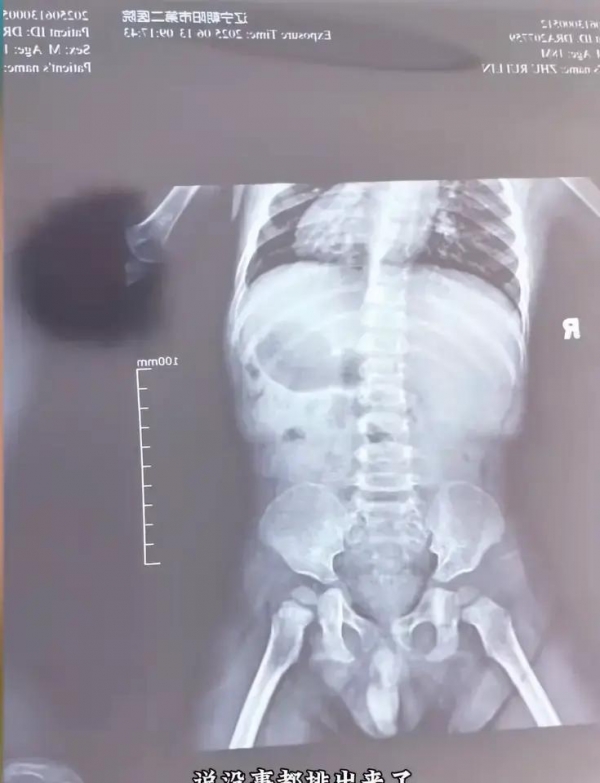

所有这些忙乱里,妈妈最后决定带佑佑赶紧去医院。医生检查后,拍了肚子的片子,发现肠道里有亮亮的水银影。医生详细看了看,说水银没弄破肠道壁,吸收风险其实不大,主要还是担心万一有中毒症状。说穿了,体温计里的水银主要有害是蒸汽被吸进去,其他皮肤碰到或是肠道吞下,没受伤基本不会被吸收。妈妈这才稍微安心一点。

怕漏掉啥细节,妈妈把网上水银相关的科普查了个遍,跟医生对上了说法,只要内脏没损伤,体温计里的水银排出来就不会有事。她直接动手,炒韭菜、煮火龙果、蒸饺子,一顿操作猛如虎,就盯着佑佑的肠道运转。这事到第二天见效,孩子如愿去卫生间,妈妈赶紧又带去医院复查,片子显示明亮的水银影子都没了,那一刻总算踏实了。